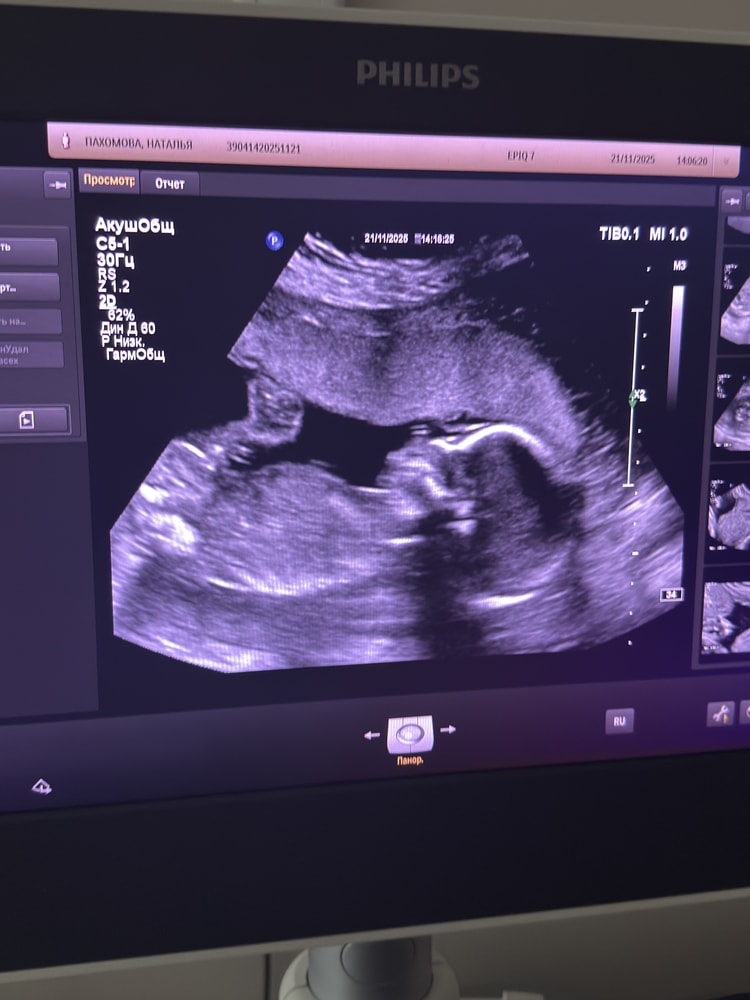

Второй скрининг 20 недель 2 дня

Сегодня сходила на второй скрининг , сказали все хорошо,вес 360 грам ,Мальчик , счастью нет придела. Уже чувствую шевеление пару дней . Понятно что точно он )))